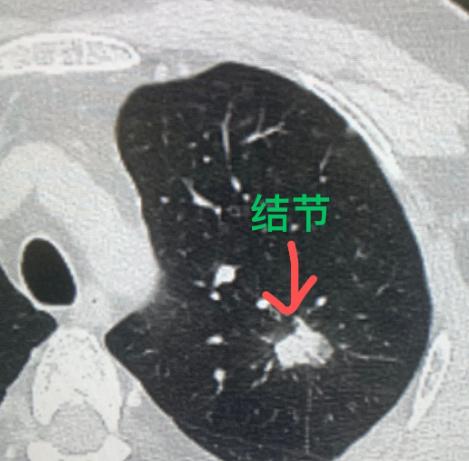

幸亏妻子拉他去了医院,才抢回一条命!肺上的问题一查出来,就已经不是早期了……

肺癌